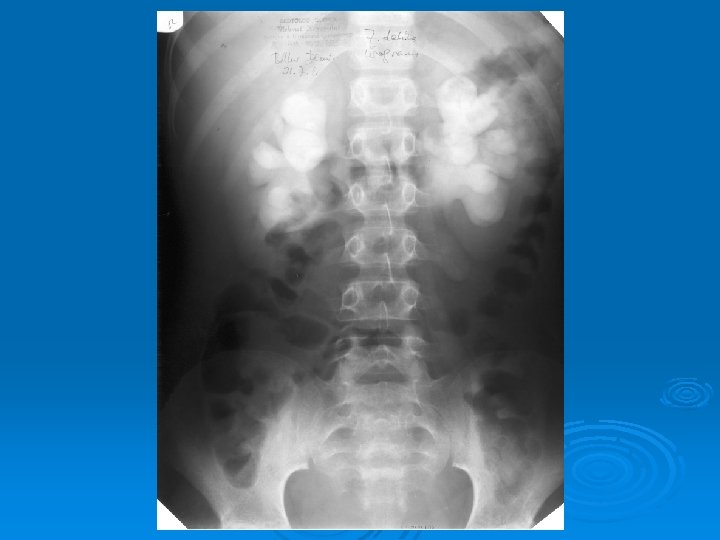

Çocukluk Çağında İdrar Yolu Enfeksiyonları İZLEMDE GÖRÜNTÜLEME GEREKEN HASTALAR Akut pyelonefrit (tüm yaş grupları) 1 yaş altı çocukta bakteriüri Erkek çocukta tekrarlayan sistit İYE ve hipertansiyon Doğuştan orta hat anormalliği

Çocukluk Çağında İdrar Yolu Enfeksiyonları İZLEMDE TANISAL GÖRÜNTÜLEME YÖNTEMLERİ Ø Miksiyon sistoüretrografisi: Vezikoüreteral geri kaçış (VÜR) görüntülenir. Ø DMSA sintigrafisi: Skar görüntülenir. Ø IVP: Tıkanıklık görüntülenir. Ø DTPA sintigrafisi: Tıkanıklık, böbrek fonksiyonları bozuk hastalarda atılım fonksiyonlarını değerlendirilebilir.